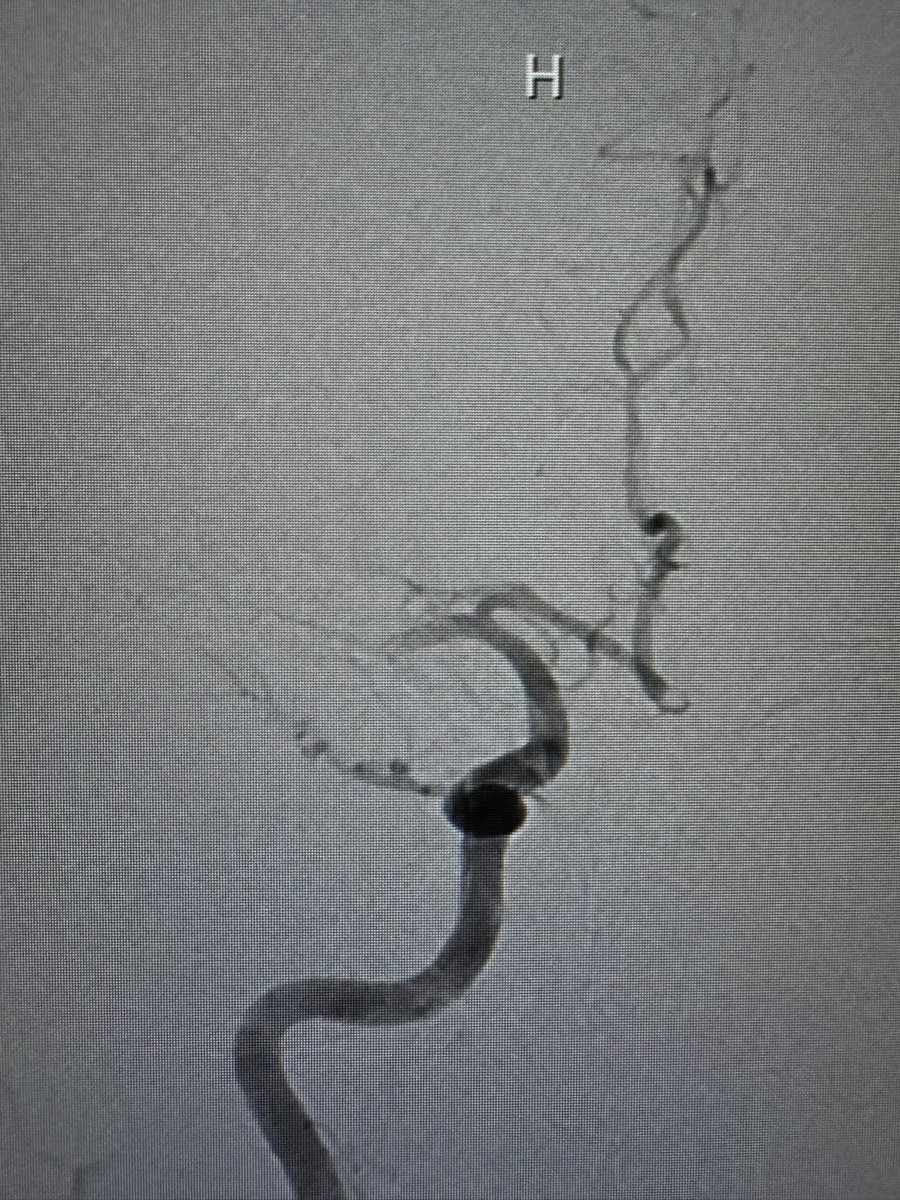

اليوم اجتزت حد الخمس الاف حاله تداخليه عصبيه قدمت فيها علاجات تداخليه عاجله ومجدوله للأمراض الوعائيه في الدماغ والحبل الشوكي وكذلك علاج الأورام التداخلي والعلاج المزمن للالم

حاله اليوم كانت سحب جلطه دماغيه حاده تكللت بالنجاح ولله الحمد

تجربه جميله تعلمت منها الكثير ودفعتني مقومات العمل والنظم الصحيه إلى تفعيل وابتكار عدد من طرق العلاج لتحقيق الفائده الكبرى للمرضى